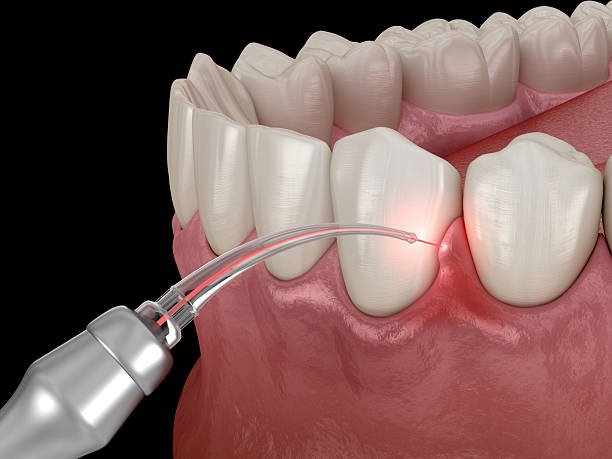

At Fort Dental Vanasthalipuram, we provide advanced Laser Assisted Flap Surgery for the effective treatment of severe gum disease and periodontal infections. This modern laser-based procedure helps remove infected tissue and bacteria with high precision, minimal pain, and faster healing.

Laser Assisted Flap Surgery is an advanced periodontal procedure used to treat deep gum infections and bone loss caused by advanced gum disease (periodontitis). Laser technology is used to clean infected areas thoroughly while preserving healthy tissue.